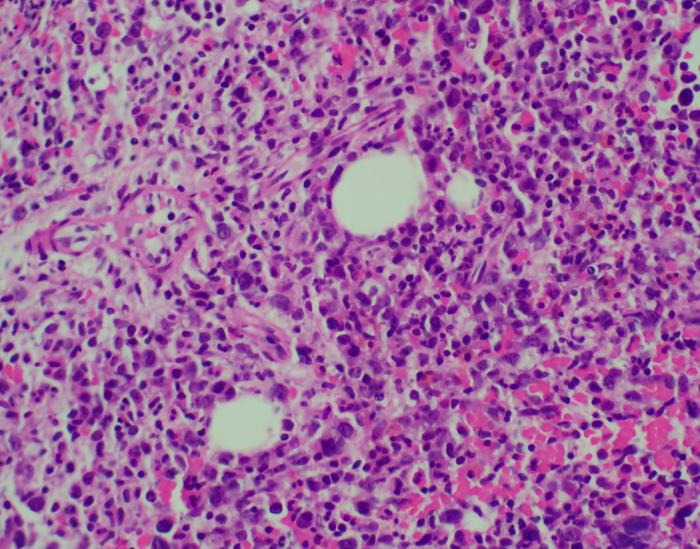

Extranodal NK/T-cell lymphoma (ENKTL) is a rare subtype of non-Hodgkin lymphoma that typically develops within the nasal cavity. Almost always associated with Epstein–Barr virus (EBV), ENKTL is more prevalent among East Asian populations than in Western populations. Prognosis is poor for patients who relapse and there is no approved targeted therapy to manage these patients. This highlights the urgent need for new and better treatment strategies.

The Lymphoma Translational Research Laboratory at NCCS has been studying the origin and cause of lymphoma, including ENKTL, with a focus on translating genomic discoveries into clinical applications. In 2020, the team discovered that some NK/T-cell lymphoma patients have a mutation in the PD-L1 gene that causes it to bind abnormally to the PD-1 gene, affecting the immune system’s ability to attack cancer cells. By treating these patients with PD-1 targeting immunotherapy, this interaction could be blocked to restore normal anti-tumoural immune system function. [1]